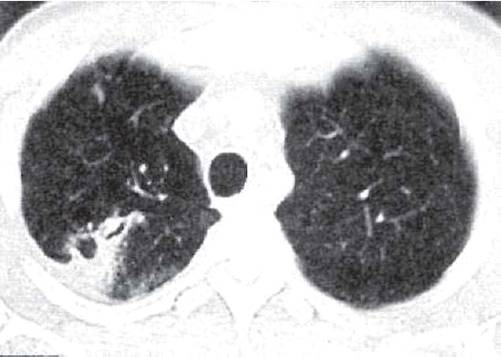

Рис. 11.9. Округлый инфильтрат в правом легком с «дорожкой» к корню. КТ.